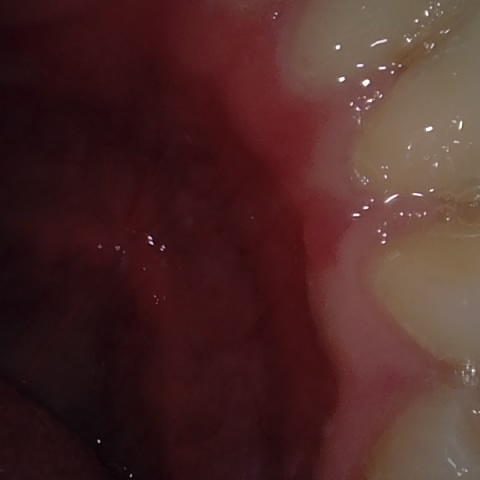

Annotated as "Bad"